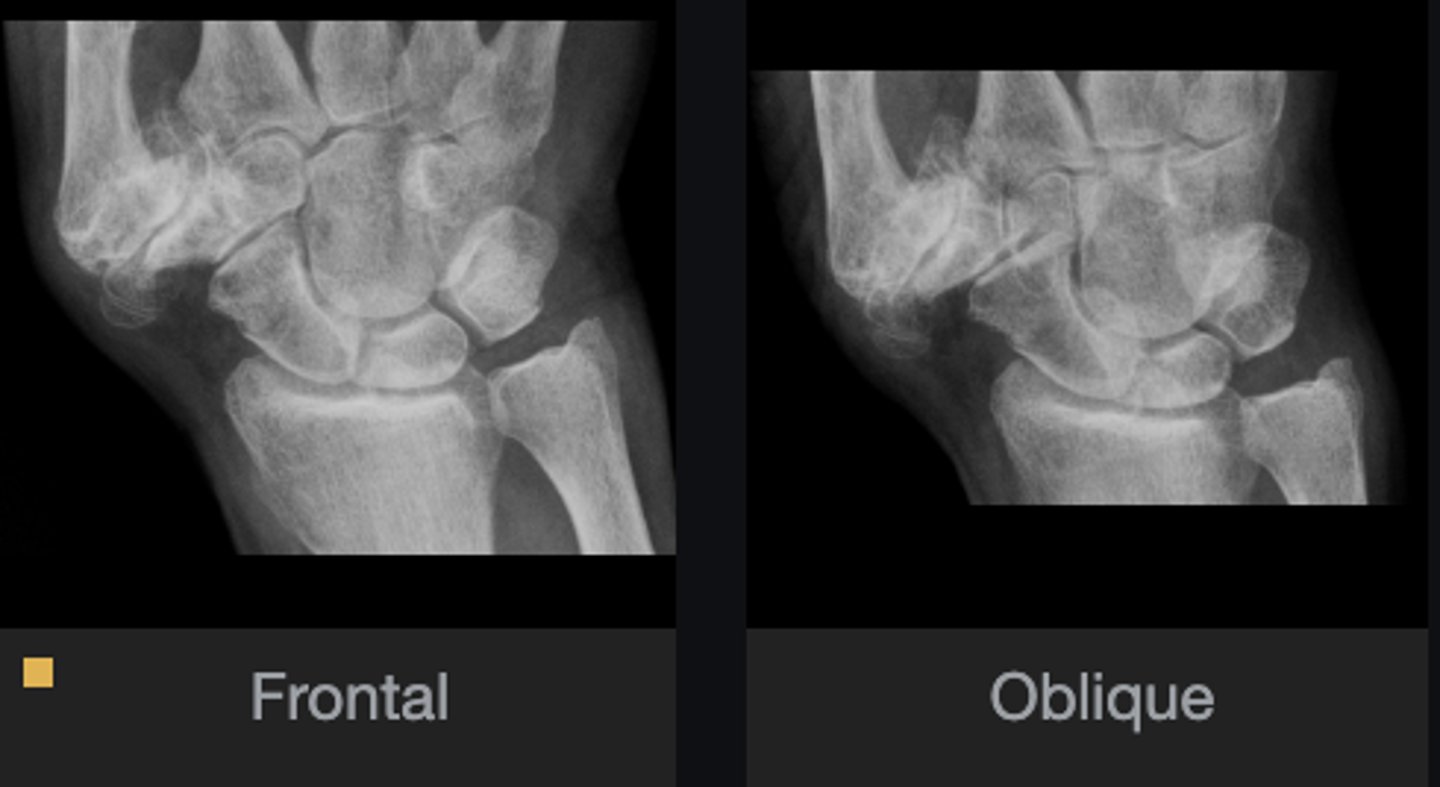

1st metarcarpal and trapezium

Bone

Carpometacarpal joint

Joint

Yes

Joint space narrowed?

No

Periarticular erosions

Osteophytes

Subchondral cysts

Subchondral sclerosis

Periarticular osteopenia

Soft tissue swelling

Intra-articular calcification

Joint ankylosis

Extra-articular calcification/osseous bodies

Subluxation

Dislocation/diastasis

Unilateral

Bilateral/unilateral

Degenerative

Category of disease

Osteoarthrosis

Diagnosis?

Correlate with patient

Next step?